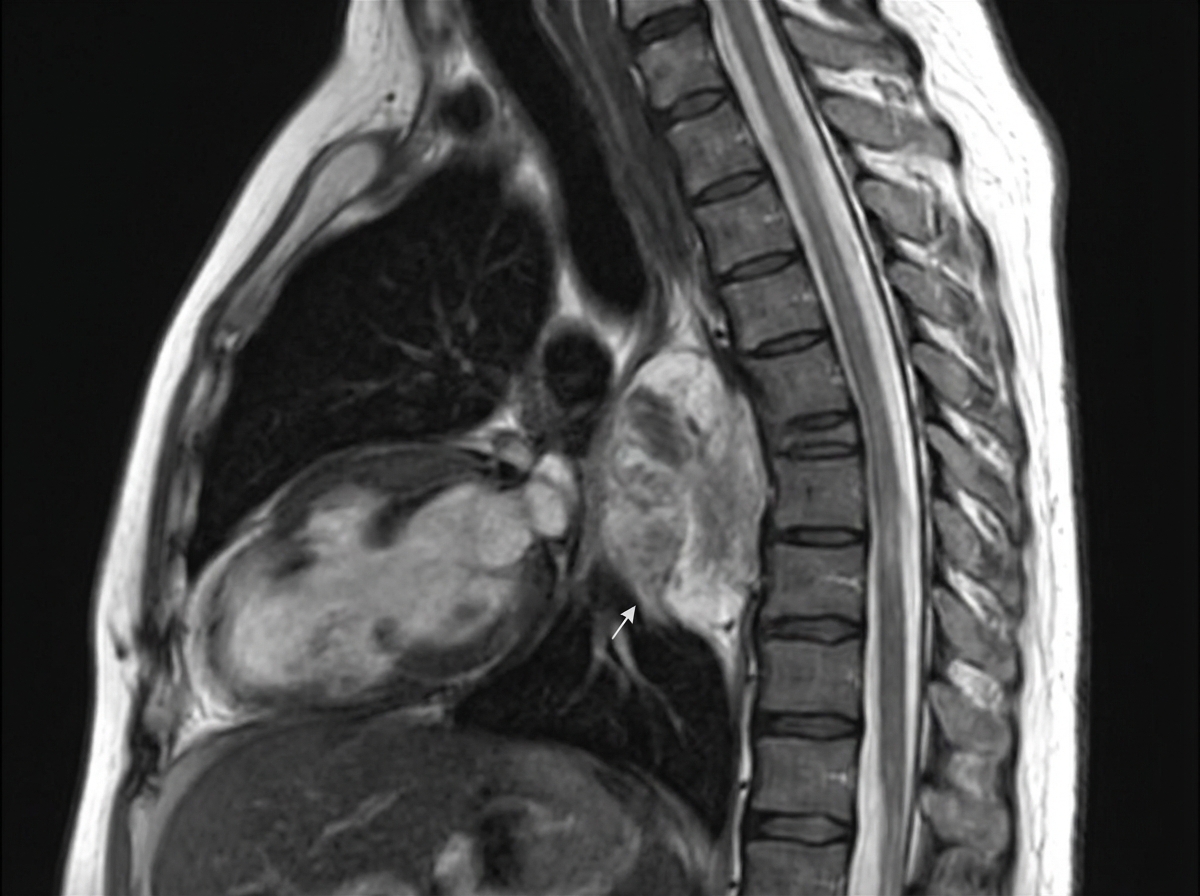

A 7-year-old girl presents with a lump in her neck which she noticed a few days ago. The patient's mother states that her daughter's left eyelid seems to be drooping, making her left eye look small. There is no significant past medical history. On neurological examination, the patient has normal bilateral pupillary reflexes but a miotic left pupil. A lateral radiograph of the chest reveals a mass in the posterior mediastinum with no evidence of bone erosion. An MRI is performed and the results are shown in the image. An imaging-guided biopsy of the mass reveals spindle-shaped cells arranged chaotically, with moderate cytoplasm and small nuclei. Scattered mature ganglion cells with abundant cytoplasm and round to oval nuclei are also present. The biopsy tissue is analyzed with immunohistochemistry and found to be positive for S-100, synaptophysin, and chromogranin. Which of the following factors is associated with poor prognosis for this patient's most likely diagnosis?